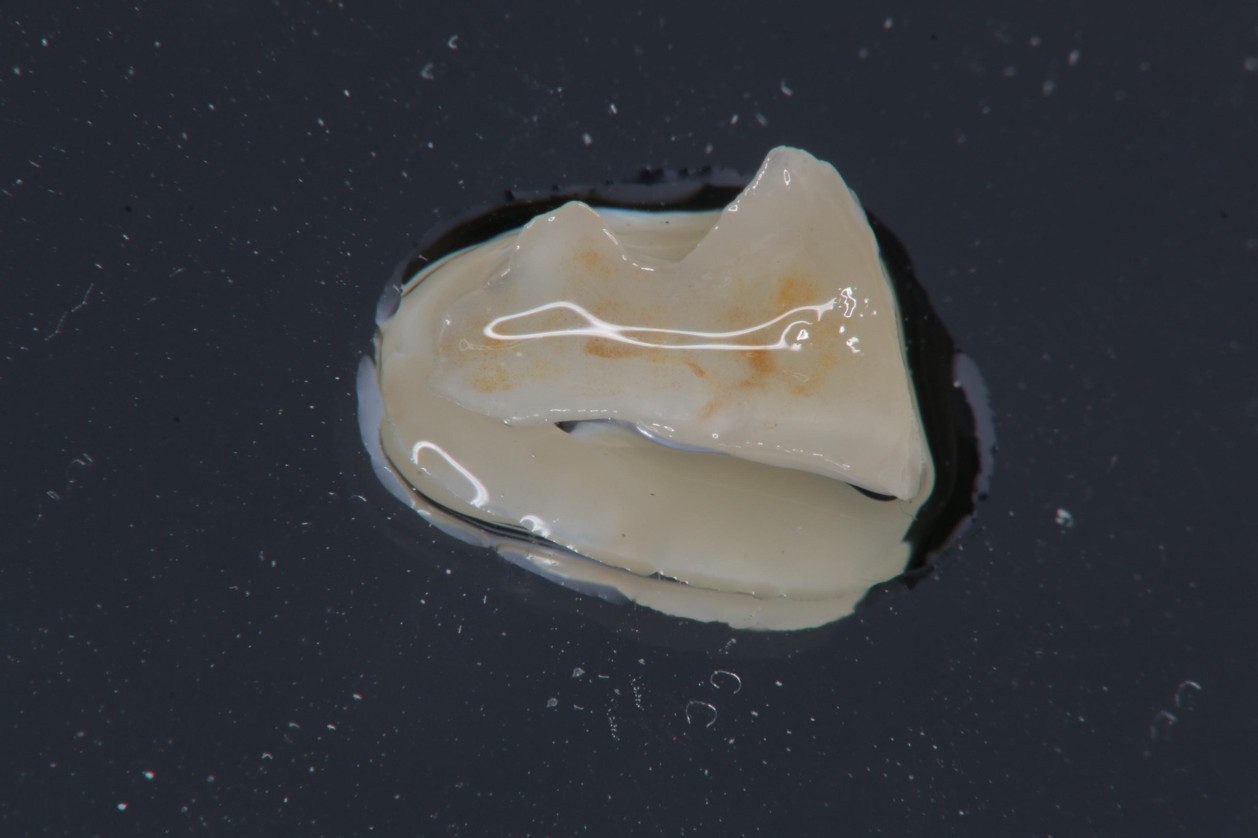

大臼齒的陶瓷崁體